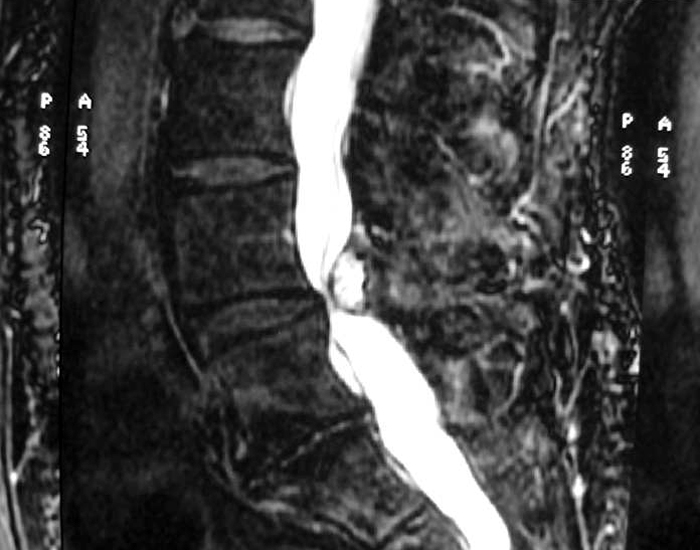

A free medical education seminar series for everyoneA FREE spine education seminar series for everyone Back pain has many faces and to many people it can be distressing, disabling or even frightening. Whether back pain comes from a strain, degenerative disc disease, a herniated disc, spinal stenosis, spondylolisthesis, a complex deformity or even a fracture, there are many options that can help you to live an active lifestyle. Additionally, osteoporosis is another disease that you may not even know you have. Learn from these dynamic experts about the various types of back problems and the latest treatments available. We will discuss the problems, the solutions and leave time for your questions to help you be active. Talk with the experts and get your concerns addressed. Spine Program